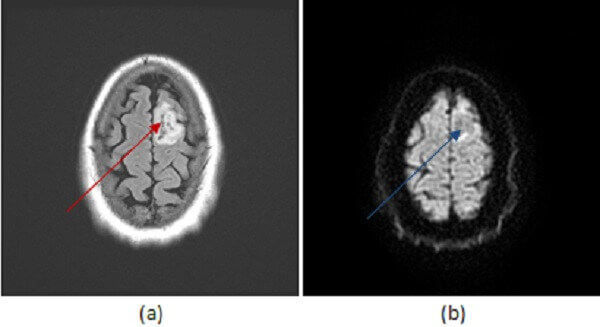

Figure 1: axial FLAIR (a, red arrow), DWI (b, blue arrow) and T1 post contrast (c ,green arrow) images of the brain reveal a circumscribed non restricting, non enhancing T2/FLAIR hyperintense mass in the high left frontal lobe.

Low grade astrocytomas are well differentiated intra-axial neoplasms. They typically present as circumscribed homogenous T2/FLAIR hyperintense supratentorial masses centered in the white matter without enhancement or restricted diffusion, although these tumors are infiltrating and microscopic disease is usually present beyond the margins apparent on imaging. There may be surrounding vasogenic edema and expansion of the cortex. Enhancement and necrosis are atypical and suggest progression to higher tumor grade such as anaplastic astrocytoma or glioblastoma multiforme.